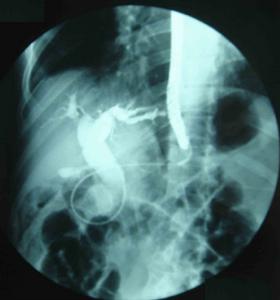

7.內鏡逆行膽胰管造影(ERCP)對梗阻性黃疸患者,在術前了解梗阻的部位和原因可提供重要診斷依據。對膽道不完全梗阻患者,可清楚顯示肝內外膽管,提示病變部位在肝門部、膽管中段或膽管下端,並清楚顯示病變程度及範圍,為手術治療提供重要依據。在膽道完全梗阻患者,ERCP僅能顯示梗阻部位的截斷征,不能顯示梗阻部位近側膽管及梗阻變的範圍;為了解梗阻近側膽管情況,有賴施行PTC檢查。ERCP檢查有引發急性化膿性膽管炎的危險,在有梗阻性黃疸病人,應非常慎重。

8.PTC檢查為進一步診斷膽管腫瘤,明確腫瘤部位的重要檢查。PTC可產生出血、感染、漏膽等多種併發症,應嚴格掌握指征,多於手術前進行。